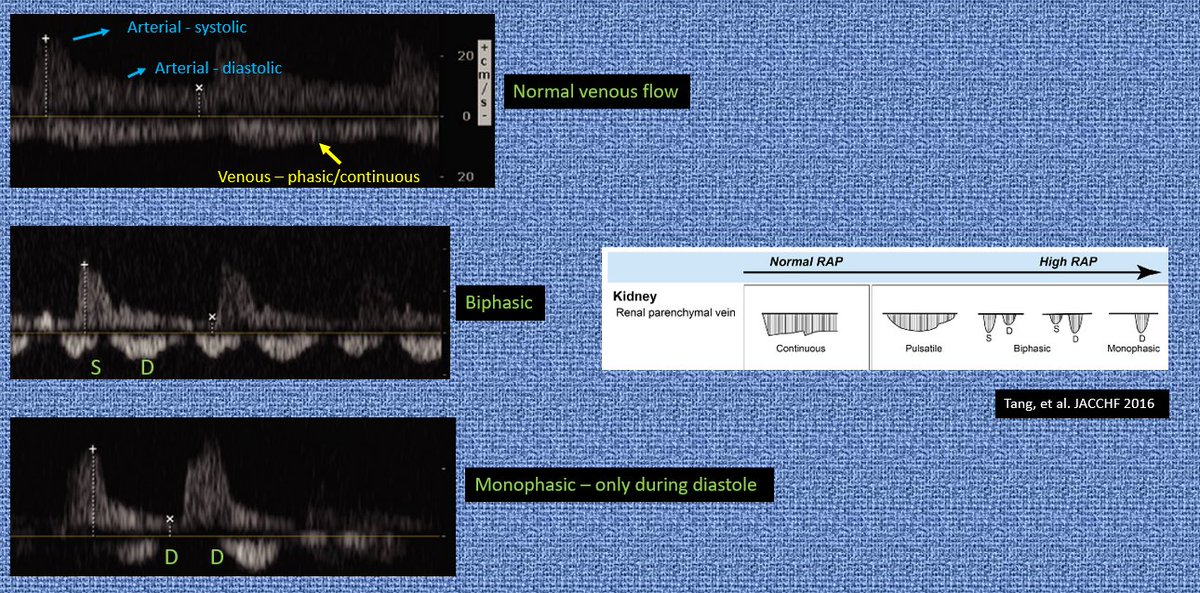

1/ Pulsatile portal v - 100% pulsatility in this case with bidirectional flow. Note the waveform change (on top) with ⬆️ RAP (Tang. et al 2016) #IMPOCUS

Note the RAP meter on top from Tang, et al. again.